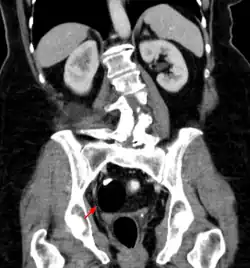

Dermoid cyst

A dermoid cyst is a mature cystic teratoma containing hair (sometimes very abundant) and other structures characteristic of normal skin and other tissues derived from the ectoderm. The term is most often applied to teratoma on the skull sutures and in the ovaries of females.